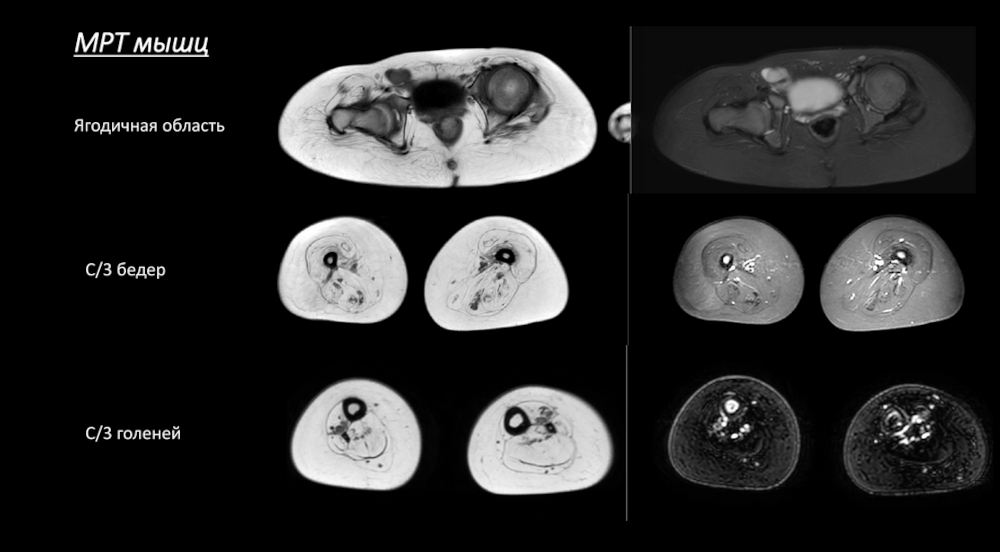

При миопатиях пациенту проводят МРТ мышц всего тела, и сотрудники МГНЦ им. Н.П. Бочкова решили проверить, что покажет МРТ у их пациентов. В частности, они проанализировали случаи заболеваний, связанных с дисфункцией тропомиозина. Это врожденные миопатии, по мере прогрессирования которых развиваются контрактуры суставов. У пациентов с заболеваниями этой группы на МРТ не было выявлено признаков фиброза или замещения мышц жировой тканью.

Еще один механизм — нарушение активности эндотелин-превращающего белка ECEL1 (фермента мышечного волокна). В этом случае болезнь связана с нарушением формирования нервно-мышечного синапса, а наследование будет рецессивным. Такие пациенты отличаются фенотипически — у них выражена центральная атрофия языка, гиперлордоз, имеются кожные складки. В данной группе МРТ-сканирование уже показало, что мышцы замещаются жиром.

Наконец, еще одна разновидность — это спинальная мышечная атрофия (СМА) с преимущественным поражением ног (SMALED). Заболевание сопровождается артрогрипозом и врожденными переломами, а его генетическая причина — это мутации в гене DYNC1H1. При SMALED происходит практически полное жировое замещение мышц, такие пациенты наблюдаются у ортопедов и переносят множество оперативных вмешательств.